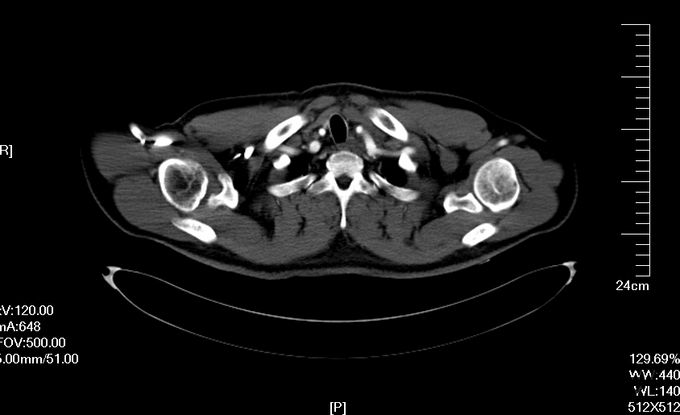

入院查体:体温36.5℃,脉搏90次/分,规则,呼吸18次/分,规则,血压150/80mmHg,胸廓正常,无胸骨叩痛。呼吸运动正常,语颤正常,无胸膜摩擦感,无皮下捻发感,叩诊正常清音,肺下界正常,双肺呼吸音粗,呼吸音对称,无罗音。心音可,心率90次/分,无杂音,腹部无压痛,无反跳痛,肝肋下未及,胆囊无压痛,Murphy征阴性,脾肋下未及,肾区无叩痛,双下肢不肿。入院后完善相关检查(胸腹主动脉CTA:主动脉夹层动脉瘤;两侧胸腔少量积液。)

予以诊断:1.主动脉夹层动脉瘤;2.高血压3级,极高危组。诊断明确后行“左颈总动脉-腋动脉转流手术+胸主动脉覆膜支架腔内隔绝术”。左侧颈部切口,游离出左侧颈总动脉,左侧锁骨下动脉,左侧椎动脉等分支。使用8mmG-tex血管一端与左锁骨下动脉行端侧吻合,G-tex血管另一端与左侧颈总动脉行端侧吻合。经右侧股动脉入路造影见主动脉夹层,破口位于左锁骨下动脉开口医院0.5cm处。左锁骨下动脉近端封闭,桥血管通畅,腋动脉及左侧椎动脉血流良好。置入美敦力胸主动脉覆膜支架(28*157mm),定位后释放。造影见胸主动脉支架释放良好。